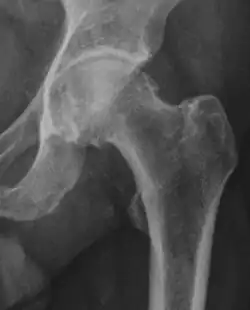

Radiograph of a cam type impingement.